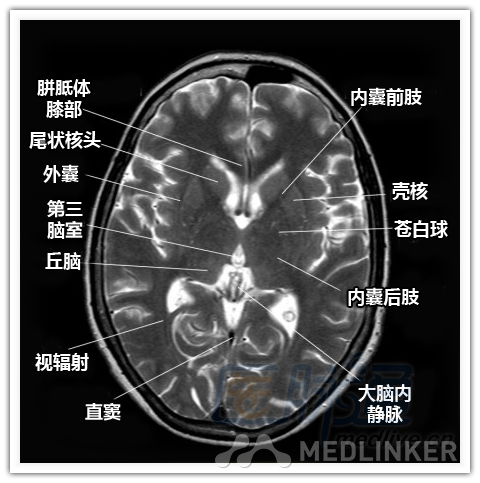

本文将对不同横断位的脑部MRI图像进行标示,主要讲解内容是脑部基本解剖。脑部横断位解剖,尤其是内囊层面的影像学解剖一直是一大重点,一起来学习一下。 现在是内囊层面了,同志们准备好了吗? 本文转载自医脉通。 声明:本文转载是出于提供更多信息以参考使用或学习、交流之目的,不用于商业用途。转载无意侵犯版权,如转载文章涉及您的权益等问题,请作者速来告知,我们将尽快做删除处理。